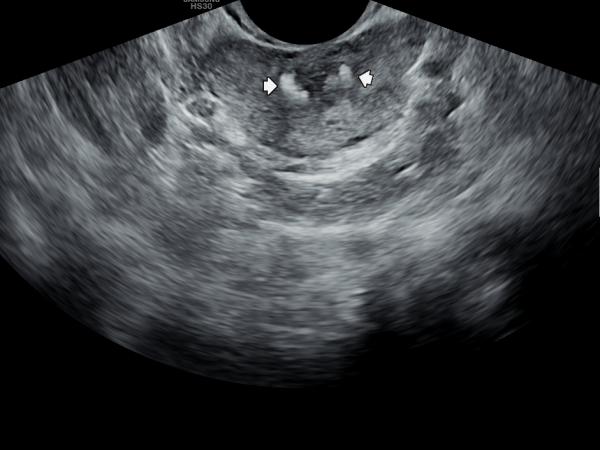

내원 첫날 정면 경직장 전립선 초음파 사진상 사정관 입구가 순환장애로 사정관의 낭종과 부분적 전립선 낭종들이 관찰되는 초음파 사진입니다.

첫 내원 당일 정면 경직장 전립선 초음파 사진상 좌우 사정관 입구에 결설이 관찰되고 전립선의 결절이 관찰되는 초음파 사진입니다.

This is a frontal transrectal prostate ultrasound image taken on the patient's first visit, showing calculi (stones) at the openings of both ejaculatory ducts and nodules within the prostate.![]()